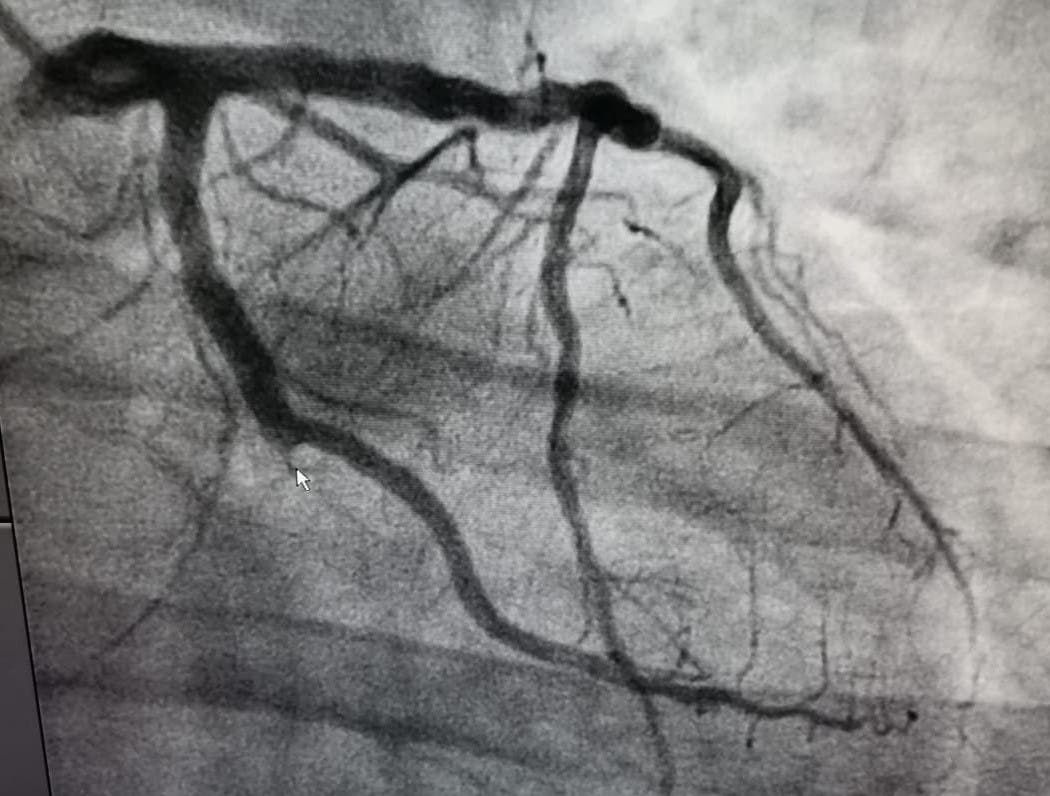

صورة توضع الجلطة القلبية الحادة للمريض